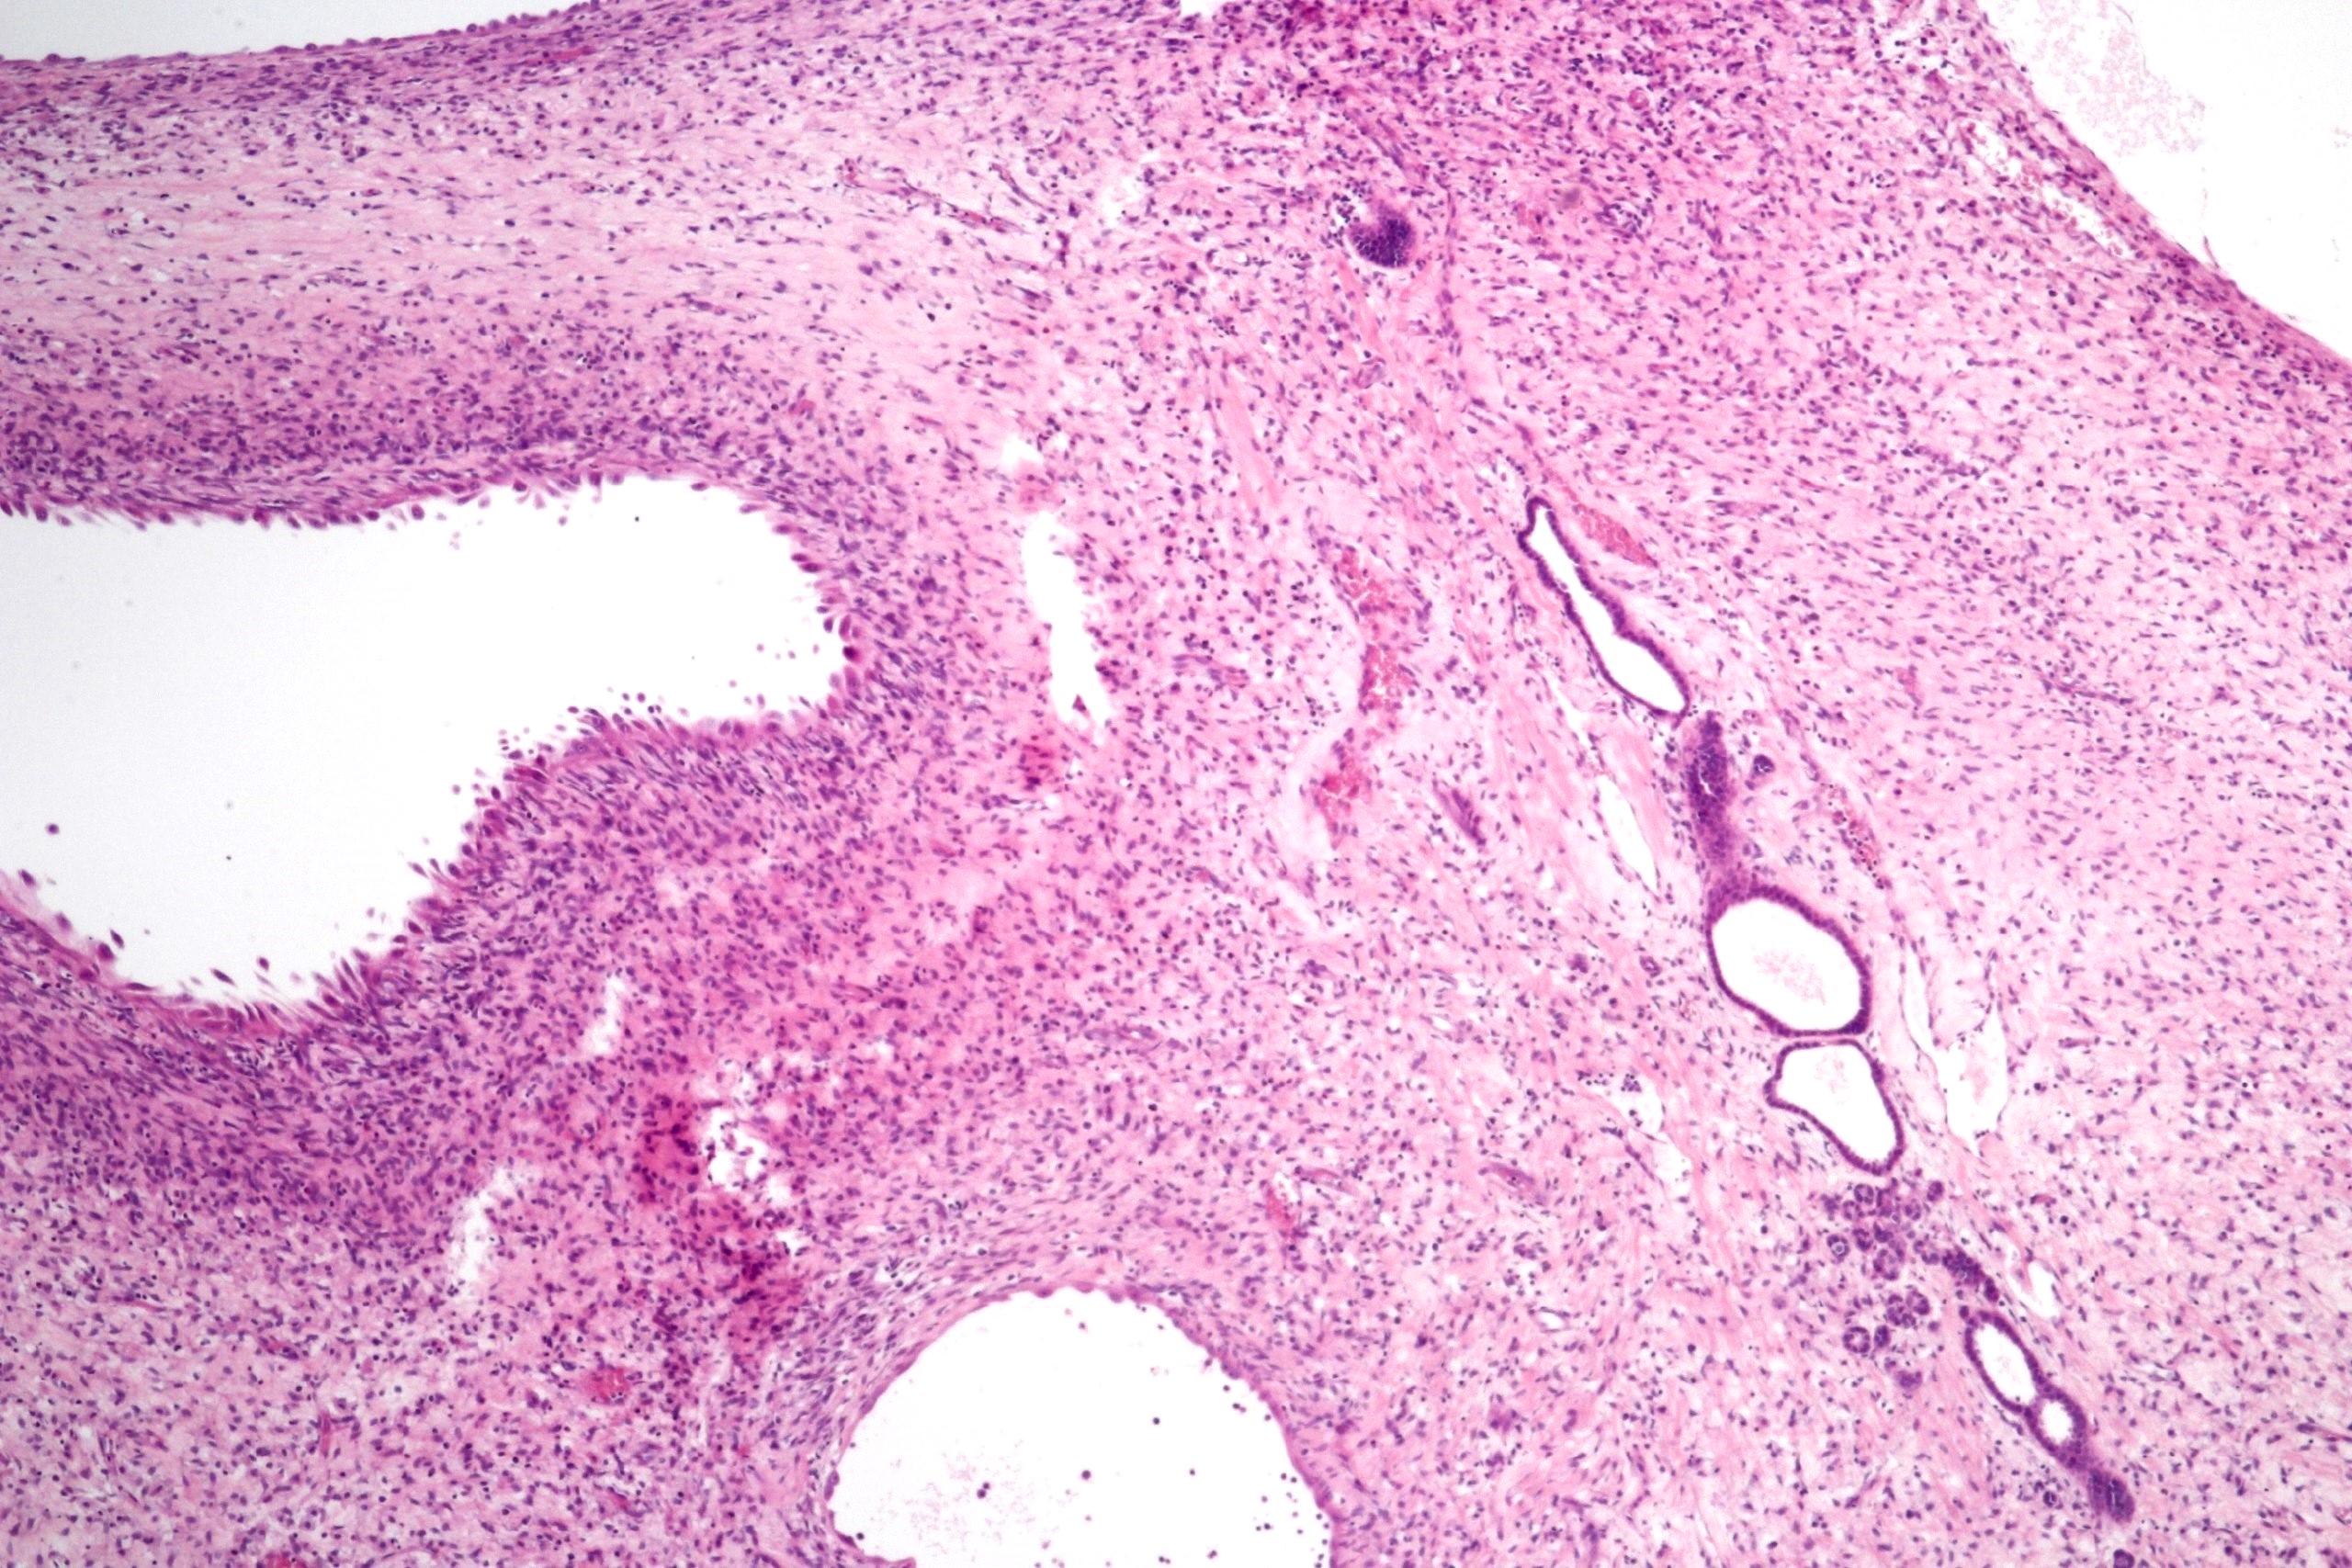

Microscopic (histologic) description

- Cysts lined with flat / cuboidal / hobnail cells (or are denuded)

- Epithelial elements consist mainly of mature and immature / abortive tubules and small papillae resembling immature glomeruli

- Key histological findings of the variably cellular septa include

- Nephroblastomatous epithelial elements

- Islands of undifferentiated blastema and differentiated mesenchymal elements (skeletal muscle and less often cartilage and fat) (J Urol 2010;183:1585)

- Focally, the septal elements may protrude into the cystic spaces in microscopic papillary folds

Microscopic (histologic) images

Contributed by Americo Brilhante, M.D. and Daniel Athanazio, M.D., Ph.D.